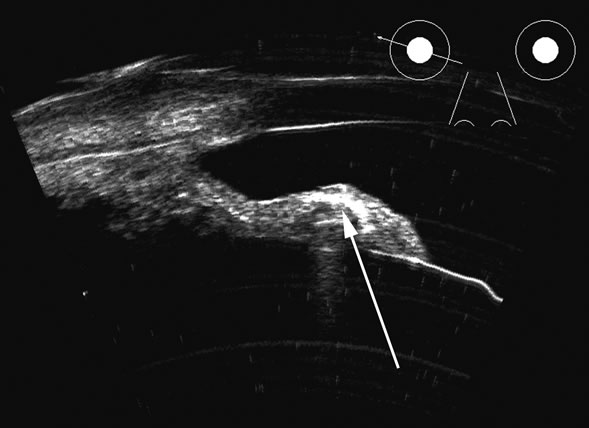

Vitreous foreign bodies are typically metal or glass objects, or intraocular lens implants. The ultrasound examination, with its better spatial resolution, is best performed following radiographic or computed tomography examinations in order to identify the location and number of foreign bodies. Ultrasonography is used to relate the position of a foreign body to the retina and lens and identify coexisting structural changes, such as retinal detachment. Metal and glass “absorb” or, more correctly, deflect sound, so that an anechoic area appears posterior to the foreign body. This area can act as an acoustic “pointer” to the foreign body (Fig. 18). A-scan or gray scale on B-scan shows a highly reflective surface of the foreign body. BBs and shotgun pellets often create a “ringing” artifact that can also act as a pointer leading to the foreign body.19 The foreign body can be easily demonstrated by lowering the gain; the foreign body remains, whereas other, less reflective tissue planes fade away due to a lower difference in acoustic impedance between tissues than metallic or glass foreign bodies. Most foreign materials have a higher density than the vitreous, and sound that passes through the foreign body may appear to move the succeeding surface forward because of the faster sound transit.

Fig. 18. A foreign body localized in the iris is easily imaged with high frequency. Characteristic trailing multiple echoes always point to the location of the body itself (arrow).